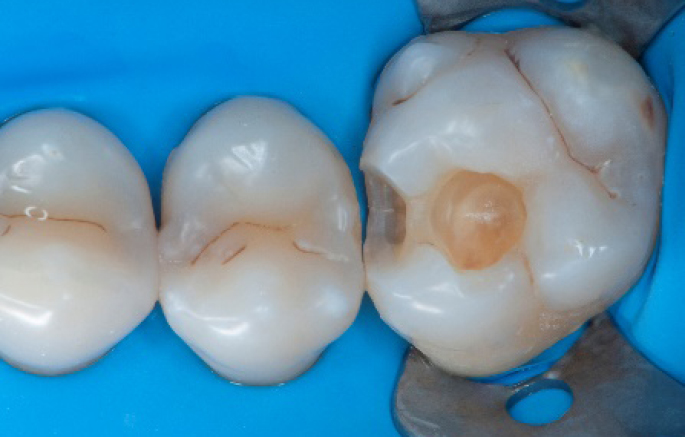

Initial situation of the patient

The patient came for a routine control appointment. She didn‘t report any symptoms but some bleeding during brushing.

Before

Initial situation: an old class I composite restoration on 1.6. New caries on the mesial wall. Presence of plaque and inflammation.